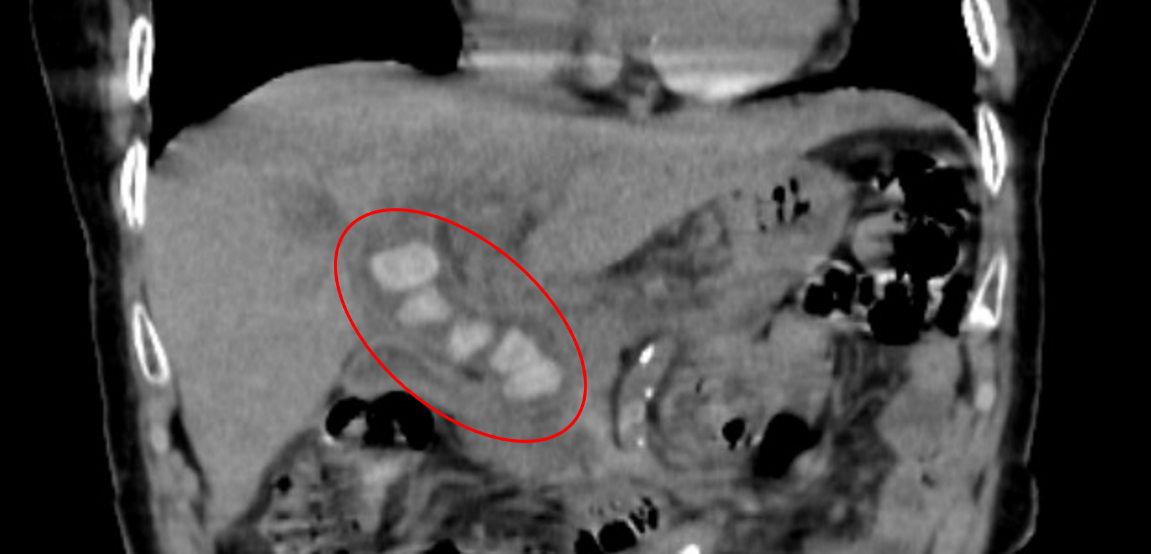

2021年9月20日下午,患者陆xx,因突发右下腹疼痛到我院消化内科一区就诊,查体右下腹有明显压痛和反跳痛,入院后急查腹部CT确诊为急性阑尾炎,...